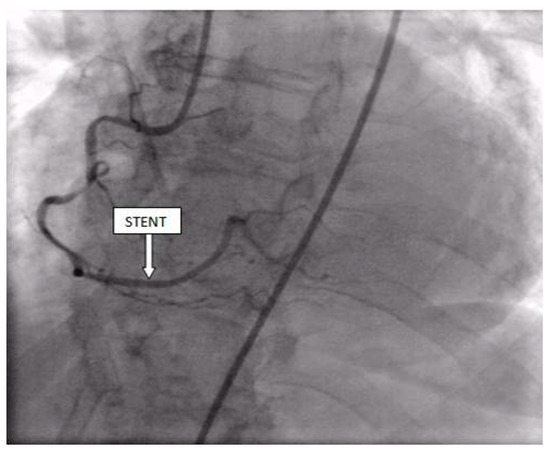

Coronary angiography was performed, showing the left coronary artery (LCA) was without significant lesions (Figure 6). On the right coronary artery (RCA), a subocclusive lesion was registered in the distal segment (Figure 7). Initially, it was thought to be a spasm, but the lesion persisted even after administering nitroglycerin intracoronary. Therefore, a primary percutaneous coronary intervention (pPCI) was performed with the implantation of a drug-eluting stent 16 × 25 mm (Boston Scientific, Marlborough, MA, USA) in the RCA, achieving the optimal result of the intervention (Figure 8).

Figure 8.

Percutaneous coronary intervention was performed, and a drug-eluting stent was implanted in the RCA, with the optimal result.